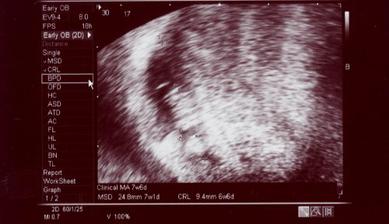

Naše krásne dievčatko